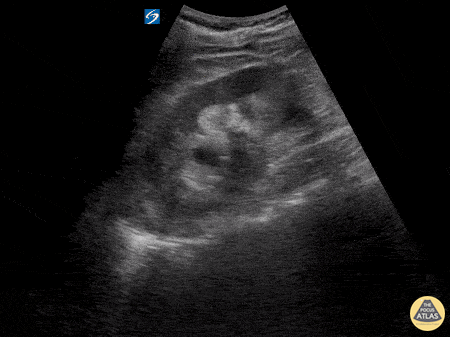

Renal/GU - Moderate Hydronephrosis from Nephrolithiasis

Here is an example of hydronephrosis in the presence of nephrolithasis. This patient presented to the emergency department complaining of new right flank pain after waking up in the morning. She was seen previously for urinary complaints, diagnosed with UTI and started on antibiotic regiment that had been altered twice due to concerns of sub-optimal coverage. She demonstrated right CVA tenderness on physical exam, raising suspicion for pyelonephritis as well as hydronephrosis. Subsequent point of care ultrasound revealed moderate hydronephrosis. CT was obtained to further evaluate and confirmed the presence of an obstructing kidney stone. Note presence of hydronephrosis as the probe is fanned/tilted through the kidney, highlighting the importance of scanning through the entire organ. Dr. Carlo Zamora, DO, PGY-1 Riverside Regional Medical Center Emergency Medicine Residency (Newport News, VA)